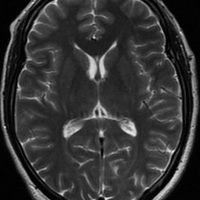

アレビアチン(フェニトイン)やデパケン(バルプロ酸)を何年も服用していると小脳に萎縮がくることがあります。小脳失調症というふらつきがでることは少ないのですが,MRIで小脳が小さくなったようにみえます。

20年以上バルプロ酸の服用をしている患者さんです。左と中央のMRIでは小脳萎縮がありますが,右側の大脳では萎縮は全くありません。小脳症状はありません。